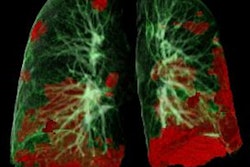

CTA of the head and neck is used in emergency situations, such as for acute ischemic stroke patients, to evaluate large-vessel occlusion; scans typically include visualizing lung apices. This visualization provides an opportunity to screen for peripheral ground-glass and consolidative opacities suggestive of COVID-19-related pneumonia.

Axial CT images from head and neck CT angiography demonstrate (A) predominantly unilateral peripheral patchy ground-glass opacities, highly suspicious for COVID-19 pneumonia and (B) bilateral and multifocal, predominantly peripheral ground-glass opacities, with subpleural consolidations abutting the visceral pleura, with additional linear opacities, very highly suspicious for COVID-19 pneumonia. Images courtesy of Stroke.They found 20 (67%) patients in the COVID-19-positive group and two (7%) in the COVID-19-negative group with lung findings highly or very highly suspicious for COVID-19 pneumonia.